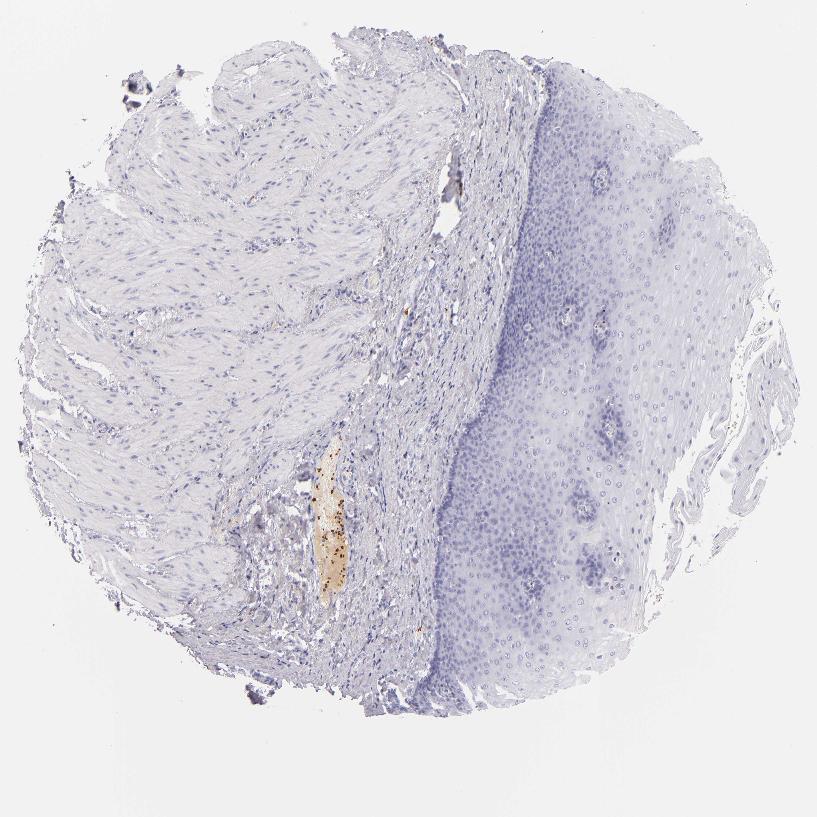

ESOPHAGUS - Antibody stainingi

Antibody staining in the annotated cell types in the current human tissue is reported as not detected, low, medium, or high, based on conventional immunohistochemistry profiling in selected tissues. This score is based on the combination of the staining intensity and fraction of stained cells.

Each image is clickable and will lead to virtual microscopy that enables deeper exploration of all samples and also displays staining intensity scores, fraction scores and subcellular localization as well as patient and tissue information for each sample.

Antibody HPA013316Antibody CAB002496

Squamous epithelial cells Not detectedNot detected